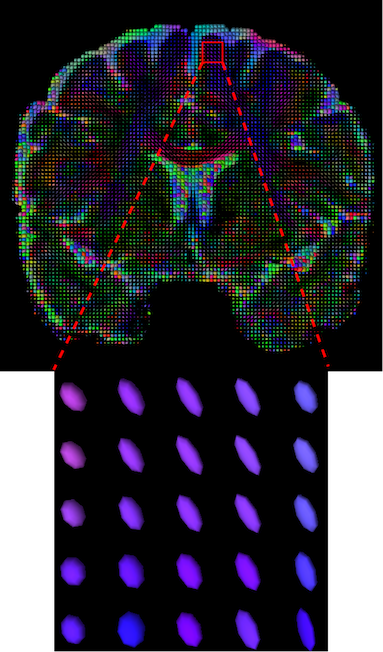

The visualization of inpainted results (showing the whole diffusion tensor for each voxel) generated from different models are demonstrated in Figure 3, where the tensor is represented in RGB coding that colours red, green and blue represent diffusion in the x, y, and z axes respectively. One typical example of reconstruction in the disrupted ROIs has been zoomed for visualization. Compared to the ground truth, TW-BAG is able to generate more distinct orientations following the original distribution and intensity across sagittal, coronal and axial views, which could demonstrate water diffusivity (denoted by eigenvalues of tensor model) more accurately. As indicated in Figure 4, the boundaries and textures of the FA map for TW-BAG are less blurry than the other competing models, validating the effectiveness of TW-BAG from a neuroscience perspective.